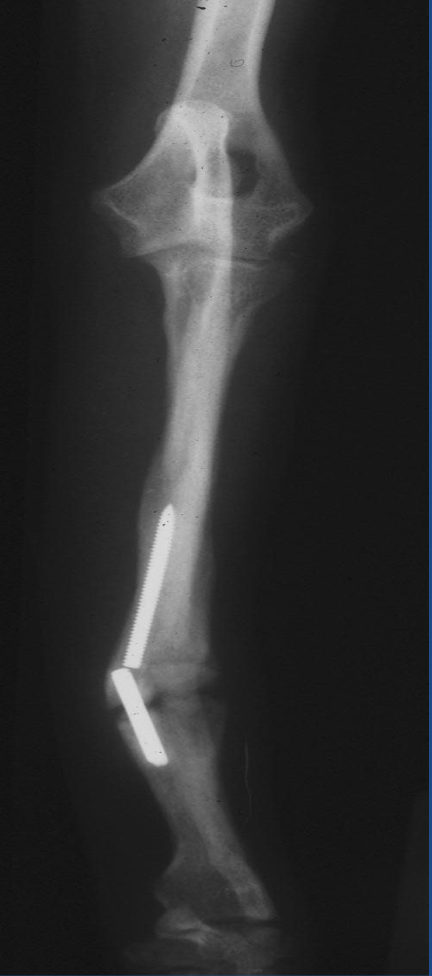

What type of nonunion case is this?

oligotrophic